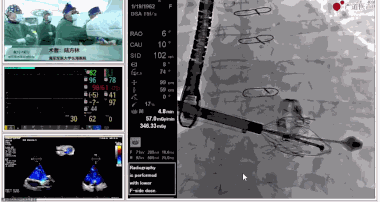

7月3日下午,海軍軍醫大學附屬上海長海醫院心血管外科徐志云、陸方林團隊在論壇中分享了經導管三尖瓣置換術(LuX-Valve®)的手術直播演示。線下會議由陶涼教授、潘文志教授、喬晨暉教授共同參與討論和臨床分享。

陸方林教授分享的是一例極重度三尖瓣返流的患者采用健世科技(LuX-Valve®)經導管三尖瓣置換系統進行的手術直播演示。此例患者為69歲女性,入院前17年行二尖瓣機械瓣置換術,術后長期服用華法林抗凝,既往“2型糖尿病”病史5年,“雙下肢水腫”3年。3個月前患者出現腹脹、雙下肢水腫,伴活動后暈厥,伴黃疽、皮膚濕癢、牙齦出血,癥狀持續加重,遂入院治療。入院后行心臟CT、心臟超聲檢查,提示:“三尖瓣關閉不全(極重度),二尖瓣置換術后,心功能III級”。徐志云、陸方林微創三尖瓣置換團隊對該患者的病情進行了充分的評估和討論。由于患者有開胸二尖瓣置換手術史,且病史時間長,同時存在相關合并癥,傳統外科手術風險極高(STS評分:8.315%),最終決定采用三尖瓣LuX-Valve®瓣膜系統對患者進行治療。

▲術中食道超聲顯示三尖瓣極重度返流

▲瓣膜植入前右心室造影

▲瓣膜植入過程

▲瓣膜植入后釋放的過程

▲瓣膜植入后三維超聲影像

▲瓣膜植入后右心室造影

在手術直播中瓣膜植入過程不到10分鐘,手術獲得圓滿成功,充分體現徐志云、陸方林團隊技術精湛,團隊協作默契及器械的優越性。